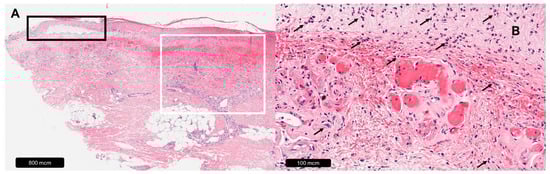

Figure 1.

Leg ulcer caused by chronic venous disease. (A) Overview, red arrow = beginning of ulceration, black asterisk = inflammatory infiltrates, blue asterisk = erythrocyte extravasate, black circle = diffuse edema. (B) Magnification, black arrows = hemosiderophages, black rectangle = fibrin cuff.